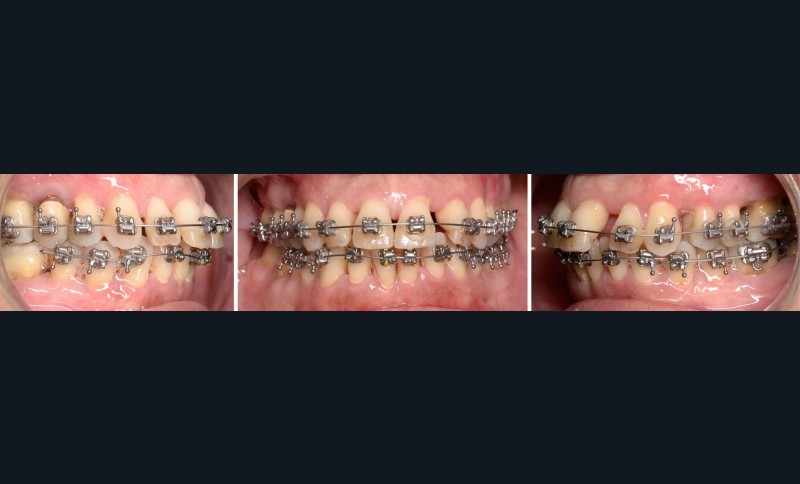

À l’examen endo-buccal (fig. 2), on note une formule dentaire complète (absence des 8) avec présence de restaurations multiples étanches, un bon contrôle de plaque et une parodontite de stade 4 grade C stabilisée [3], des récessions gingivales et des mobilités dentaires généralisées (degré 2, classification de Miller). L’arcade mandibulaire présente une courbe de spee importante avec égression du bloc incisivo-canin. Les milieux inter-incisifs sont alignés, le recouvrement est normal, le surplomb est augmenté à 3 mm et associé à des diastèmes et de la vestibulo-version des incisives maxillaires. Les relations antéro-postérieures canine et molaire sont en Classe I d’Angle.

Le traitement d’orthodontie est réalisé en technique multi-attache vestibulaire (TGO, GC Corporation, Tokyo, Japon). La dent 46 n’est pas prise en charge dans l’appareillage, étant donné son faible ancrage et son pronostic réservé. L’alignement initial est effectué sur un arc Niti .016 au maxillaire et en trois segments à la mandibule (Niti .018x.025 en postérieur et Niti .016 de 33 à 43) (fig. 6).